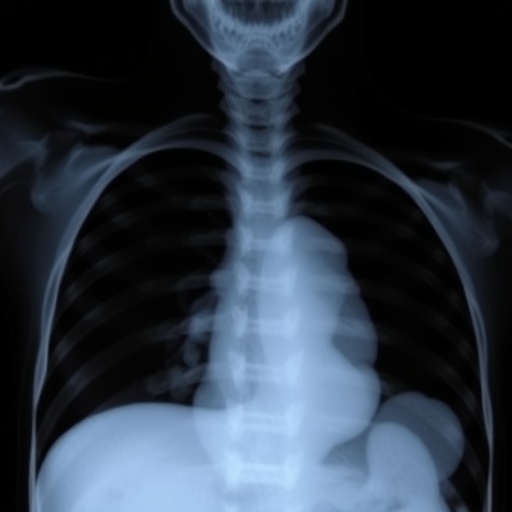

The investigators also explored biochemical markers and imaging findings, correlating these with clinical endpoints. Abnormalities in pulmonary function tests, elevated inflammatory cytokine levels, and characteristic radiographic features were all associated with worse outcomes. By precisely characterizing the pathophysiological milieu of severe BPD, this work bridges the gap between bedside observations and underlying molecular mechanisms. Such a translational approach paves the way for targeted therapies that could alter the natural history of the disease.